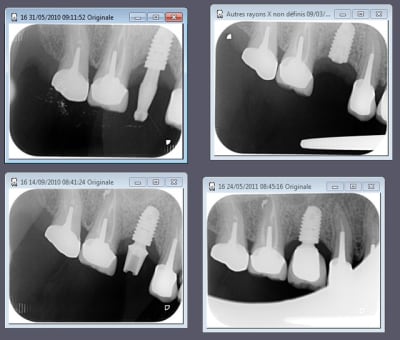

EII et Mise en vitrine immédiate, ici implant très enfoui, premier cliché à 3 mois post-op puis à un an (il faut préciser que le contrôle de plaque est plus que parfaitement réalisé par le patient).

(implant Dentium superline avec état de surface SLA)

cas d'un axiom avec perte crestale et mise en charge en septembre voila l'évolution dans le temps la suite dans six mois

Une belle cratérisation!!!!